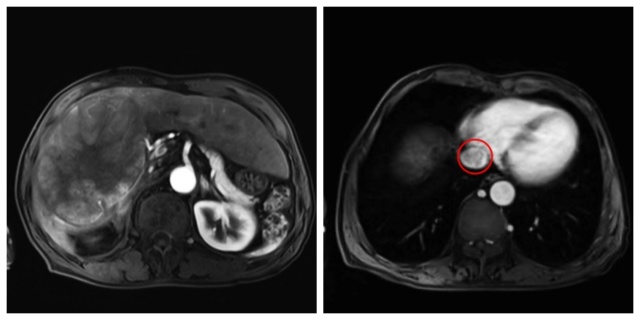

▲术前影像显示巨大右肝肿瘤及下腔静脉癌栓(接近右心房水平)

患者为67岁男性,体检发现肝脏一个直径达14.3厘米的巨大肝癌,肿瘤不仅包绕了关键的第二肝门结构,同时侵入下腔静脉形成广泛癌栓,且癌栓向上延伸至极高危位置——接近右心房入口。这一复杂的病情使肿瘤被判定为初始不可切除,手术面临难以逾越的技术挑战和极高的致命风险(如术中大出血、癌栓脱落导致肺栓塞或肿瘤广泛播散等)。

经过6周期的精心治疗,转化效果令人鼓舞:肿瘤直径由14.3cm缩小至9.0×7.4cm,更为关键的是,原本延伸至近心房的极高危癌栓成功向下退缩至第二肝门水平下腔静脉主干。影像学评估确认转化治疗目标达成,患者迎来了宝贵的手术根治机会。为确保手术安全可行,科室再次启动MDT机制,联合麻醉科、血管外科、心外科、重症医学科、肿瘤科、感染性疾病科、消化内科进行多学科会诊。专家们对转化效果、患者耐受性及手术预案进行了全面、严格的再评估。综合研判认为,肿瘤降期效果显著,癌栓位置已相对安全可控,患者全身状态可耐受重大手术,具备明确的手术指征且无绝对禁忌症。最终决策实施右半肝切除联合下腔静脉切开取栓术。